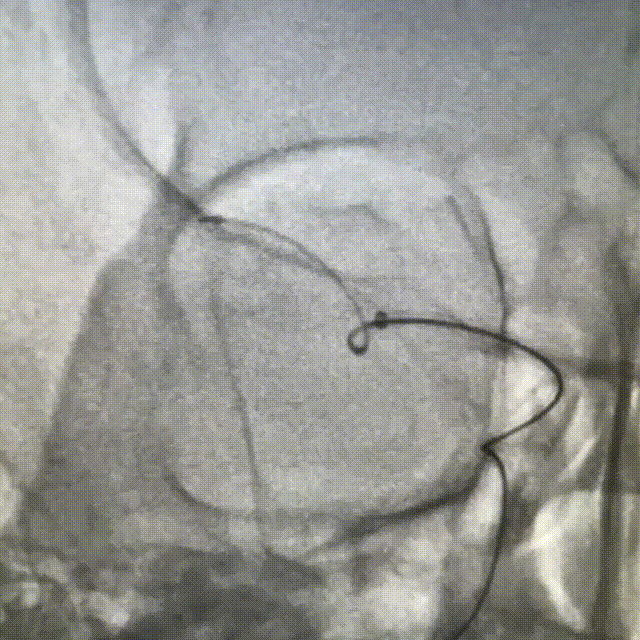

支架输送及定位:

经QUEEN-track微导管将4.0mm*25mm Neurohawk取栓支架输送至病变部位,直至支架远端显影超过血栓,定位时确保血栓位于支架有效长度的中后段。

支架释放:

固定支架推送杆,缓慢回撤微导管,释放Neurohawk取栓支架,微导管的头端必须撤至显影段远端露出。支架后程释放时,支架推送杆给张力的同时回撤微导管。Neurohawk取栓支架全身通体显影,可以通过3根显影丝,观察支架打开情况,支撑性较好。

WAVE-track颅内血栓抽吸导管上行至大脑中动脉M1段后,负压抽吸,抽拉结合,取出血栓。WAVE-track颅内血栓抽吸导管0.070inch大口径内腔,血栓抽吸能力强;管体近端PTPE,远端超柔软材料兼顾支撑性和到位性,易推送抗扭折。